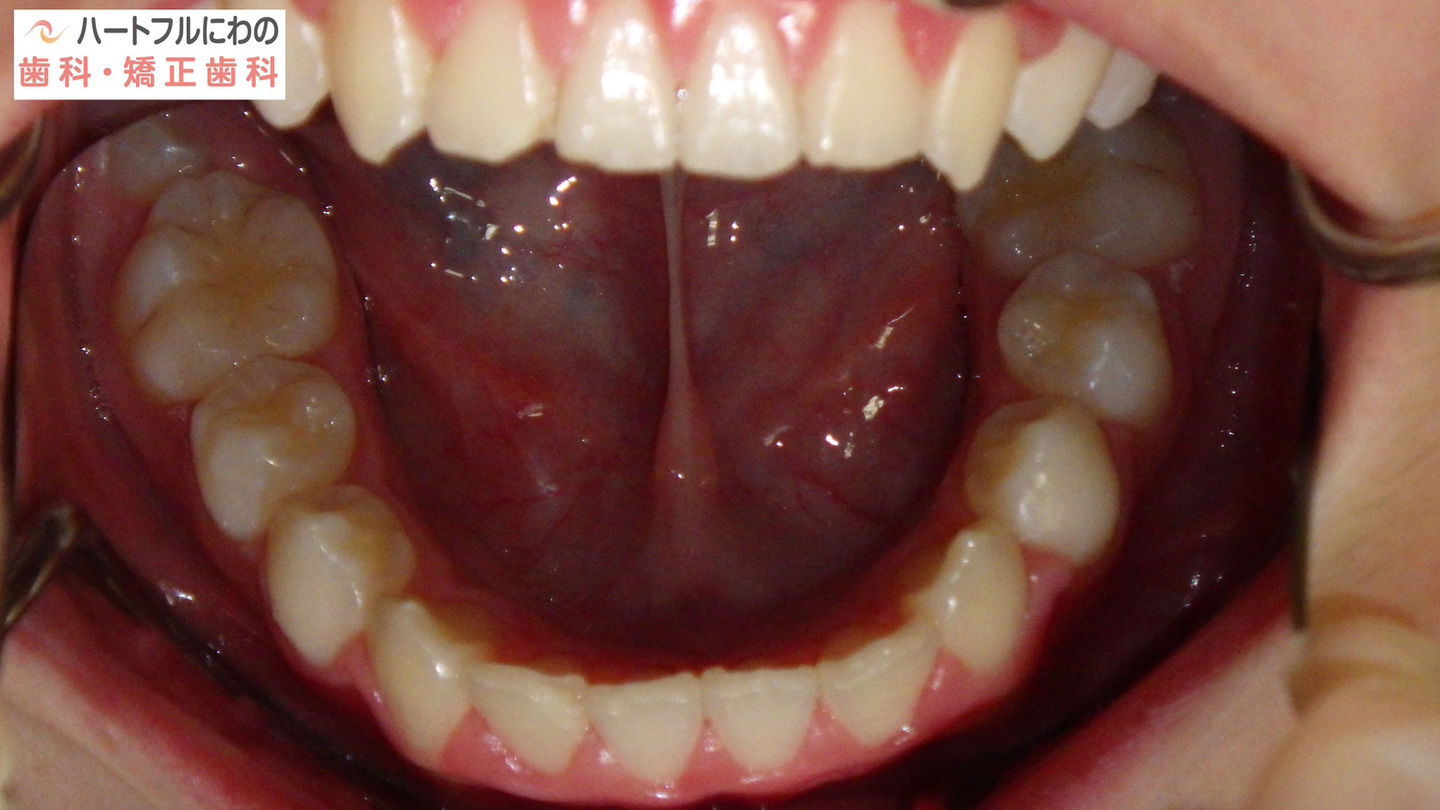

奥歯と前歯の前後的位置関係は大きく改善し、正常になりました。

細かい部分の修正や緊密な咬み合わせを作るための二期治療(仕上げ)は一年以内で終了予定です。